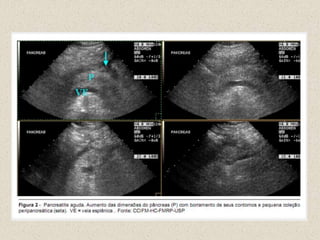

ULTRA SOMPesquisa de colelitíaseAvaliação de coleções

USG